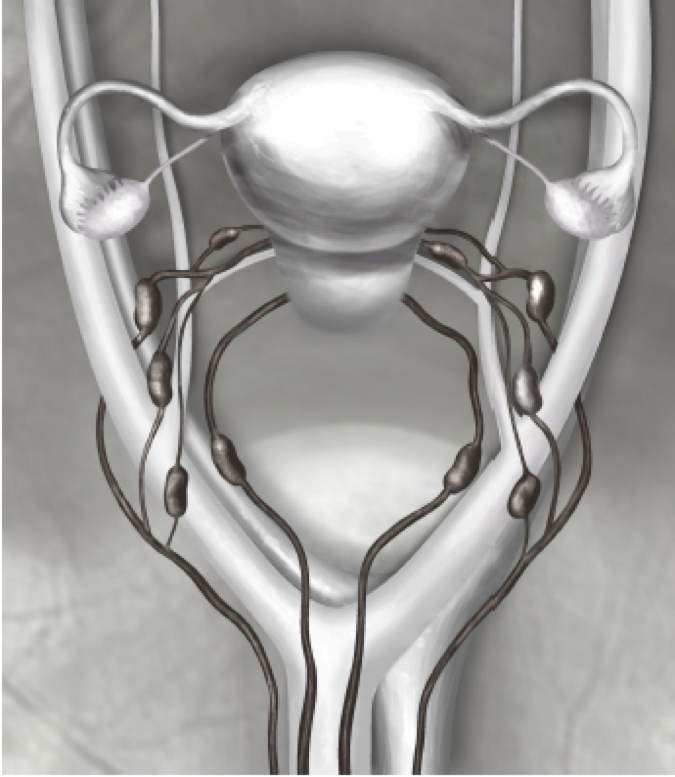

Detektion av portvaktslymfkörtlar ska ske längs de övre paracervikala banorna medan detektion av portvaktslymfkörtlar längs de nedre paracervikala, presakrala banorna, vilket också är tekniskt mera komplicerat, kan undvaras då risken för isolerade körtelmetastaser presakralt är mindre än 3 % (avvakta publikation).

Detektion av portvaktskörtlar ska utföras innan hysterektomin och inleds med injektion av 4 x 0,25 ml, 2,5 mg/ml indocyaningrönt (ICG) klockan 2, 4, 8 och 10 långsamt submuköst i cervix. Därefter öppnas de pararektala och paravesikala avaskulära spatierna på sådant sätt att den parauterina lymfovaskulära vävnaden med lymfbanor från uterus till bäckenväggarna behålls intakt. Därefter bedöms ICG-upptaget i lymfbanor och lymfkörtlar. Ipsilateral reinjektion av ICG rekommenderas vid uteblivet ICG-upptag.

Två typer av ICG-baserade portvaktskörtlar kan definieras: typ 1 utgörs av ICG-positiv körtel med en afferent ICG-positiv lymfbana, medan typ 2 definieras som en ICG-negativ lymfkörtel med en afferent lymfbana i avsaknad av andra ICG-positiva ipsilaterala körtlar. Parallella lymfbanor förekommer frekvent och en detektion av portvaktslymfkörtlar ska alltid innefatta bedömning av körtlar i obturatorlogen (den vanligaste lokalisationen för isolerade körtelmetastaser) och körtlar medialt och lateralt om a. iliaca externa. I tillägg ska makroskopiskt misstänkta körtlar oavsett ovanstående alltid avlägsnas.

Den parauterina lymfovaskulära vävnaden (PULT) förbinder uterus med körtlar mera lateralt och innehåller körtlar i upp till 40% av patienterna. Om körtlar identifieras makroskopisk bör dessa avlägsnas och histologiskt behandlas som SLNs.

I avsaknad av portvaktskörtlar typ 1–2 definierade enligt ovan, kan lymfkörtlar på anatomiskt typiska lokalisationer utföras (portvaktskörtel ”anatomi”). Detta bör alltid omfatta körtel i proximala obturatorlogen, körtel interiliacalt och körtel lateral om a. iliaca externa i nivå-bifurkation av a. iliaca communis (de typiska lokalisationerna). Se figur 5.

Figur 5. Schematisk beskrivning av typiska positioner för portvaktskörtlar vid livmoderkroppscancer

Luhrs Bollino Persson Gynecol Oncol 2022 Jun;165(3).